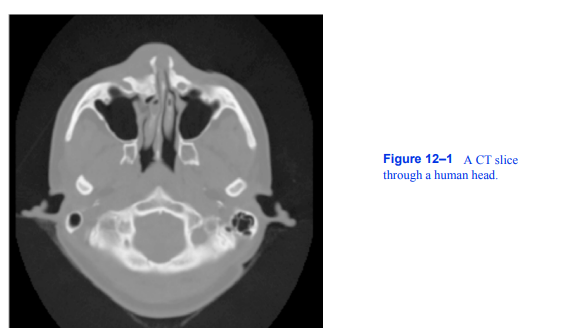

图12-1人脑CT切片。

本案例研究涉及CT数据。计算机断层扫描测量x射线穿过人体时的衰减。CT图像由灰色级别组成,从黑色(空气)到灰色(软组织),再到白色(骨骼)。图12 - 1为头部CT横切面。这个切片是垂直于脊柱的,大约穿过耳朵的中部。头部周围的灰色边界清楚地显示出耳朵和鼻梁。切片内部的深色区域是鼻道和耳道。亮的部分是骨头。这项研究包含93个这样的切片,间隔1.5 mm。每个切片有2562像素,间隔0.8毫米,12位灰度。